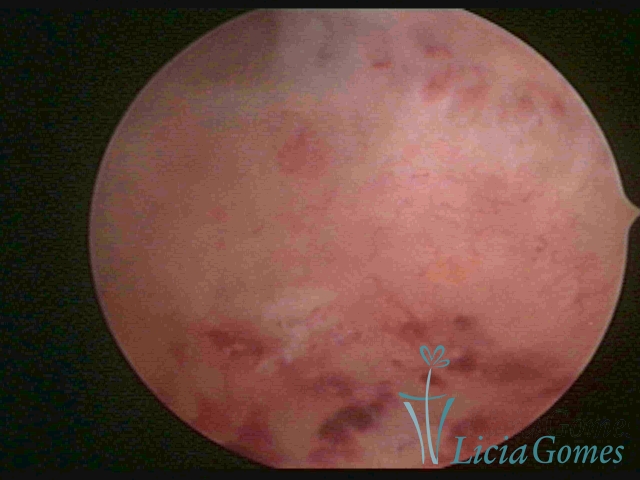

CHRONIC ENDOMETRITIS

The surface of the endometrium may present changes such as a red punctuate forming vascular balls, a smooth, hypervascularized endometrium or intensely presenting red areas, with accurate edges and yellowish white spots in its interior, providing a "STRAWBERRY PEEL" aspect, a pale yellow color of fundic and lateral commissures, in contrast with the intense red color present in the walls.